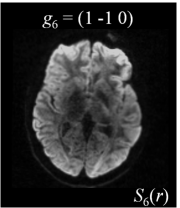

Six axial DW measurements and one non-DW image are shown in Figure 1, along with the corresponding magnetic field gradients . Note the difference in intensity values for different gradient directions.

| (a) | (b) | (c) | (d) |

![]() |

| (e) | (f) | (g) | (h) |